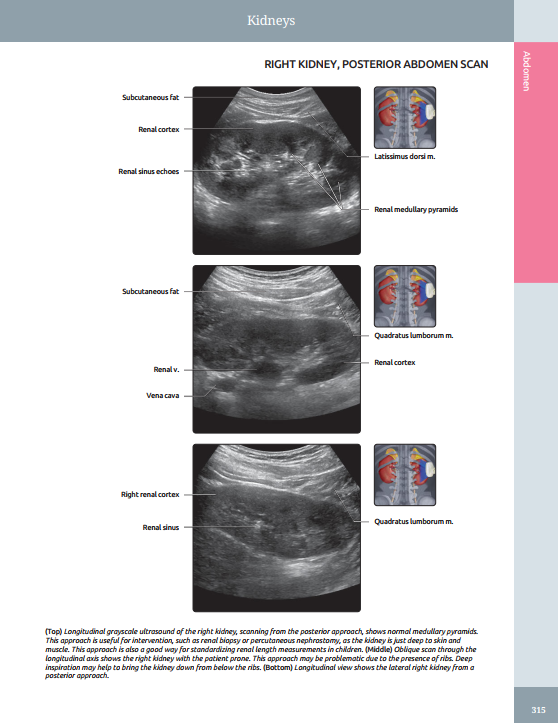

Presents richly labeled images with associated commentary as well as thumbnail scout images to show transducer placement

Features a robust collection of CT/MR correlations, highlighting the importance of multimodality imaging in modern clinical practice